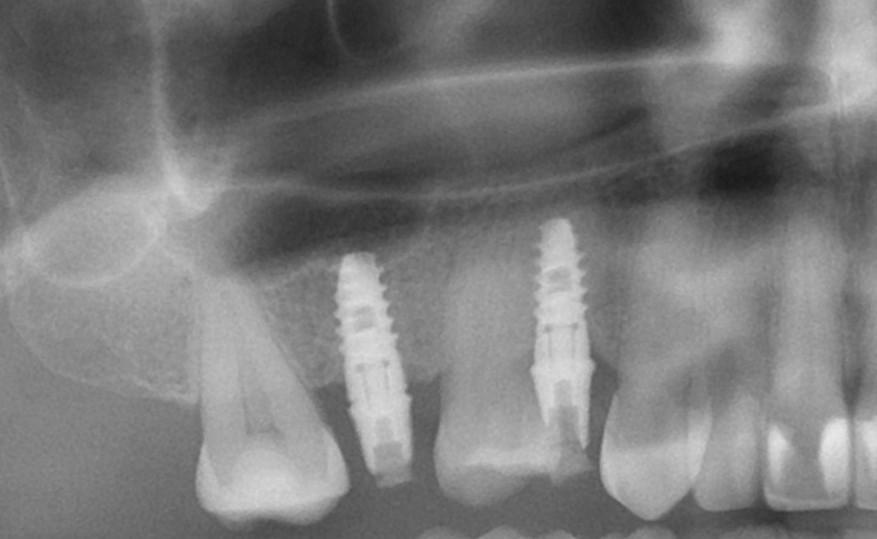

- выполнение компьютерной томографии и ортопантомограммы;

Полное приживление титанового корня занимает значительное время, и стоит отметить, что на нижней челюсти этот процесс происходит быстрее. Это связано с особенностями структуры кости — нижняя челюсть более плотная и массивная, поэтому остеоинтеграция занимает около 3-4 месяцев.

Верхнечелюстная кость относится к воздухоносным тканям и имеет более рыхлую структуру, что приводит к тому, что процесс приживления может занять до 6 месяцев.